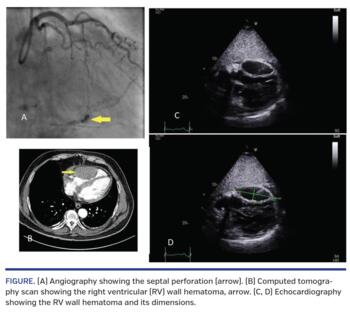

A 65-year-old male was undergoing right coronary artery (RCA) chronic total occlusion (CTO) percutaneous coronary intervention (PCI) with dual-arterial access of the right radial and right femoral arteries. An initial antegrade approach using wire escalation was unsuccessful, with wire exit distally. A retrograde approach through a septal collateral with a microcatheter was undertaken with difficulty advancing the microcatheter and evidence of perforation of the septal collateral (Figure 1A), with the patient complaining of chest pain and ST-segment elevation on electrocardiogram. The septal branch had to be coiled to achieve hemostasis.

Echocardiogram showed a 3 x 7 cm mass in the right ventricle (RV) wall (Figures 1C and 1D). There was a trivial rim of pericardial fluid. Subsequent computed tomography (CT) scan demonstrated a 4 x 7 cm hematoma within the anteroinferior portion of the RV (Figure 1B). Pericardial fluid tracked up into the mediastinum to the level of the aortopulmonary window and the pretracheal region. The patient remained stable and was managed conservatively and was discharged home 3 days later. Repeat echocardiogram 4 weeks later showed the hematoma remained at the same size; echocardiogram and cardiac CT are planned in 6 months to assess the resolution of the hematoma.